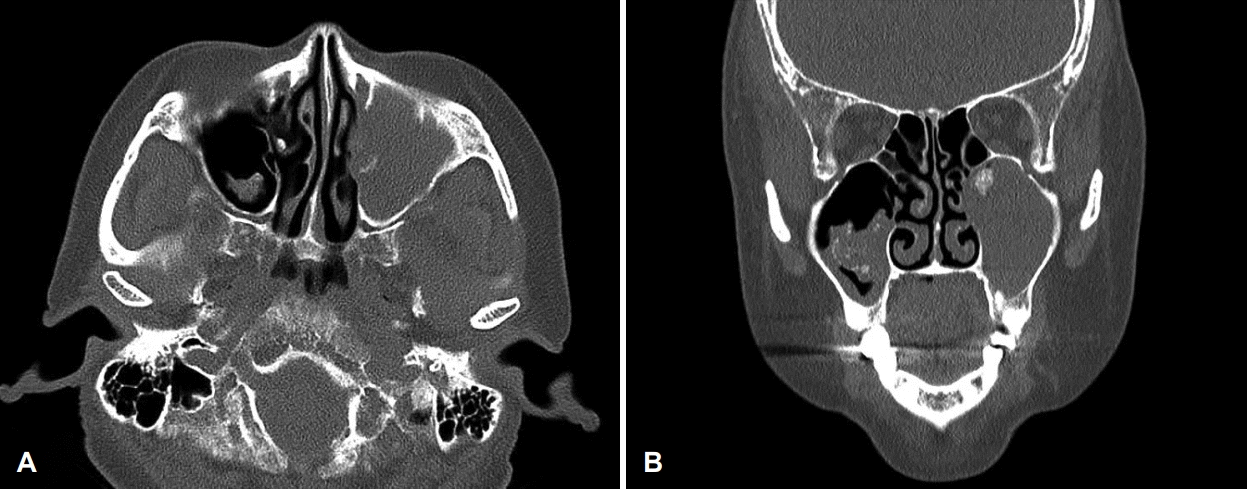

64세 여자 환자가 내원 5주 전 외부 치과에서 치아 신경치료를 받던 중 좌측 상 잇몸 및 안면 부종이 발생하여 콘빔 전산화단층촬영을 시행하고 절개 배농을 시도하였으나 실패하였다. 이에 영상상 발견된 부비동염 소견으로 타 외래에서 내원 2주 전 부비동 전산화단층촬영을 시행 후 양측 상악동 부비동염 의심 소견으로 내원하였다. 환자는 기저질환으로 고혈압, 당뇨 외 1992년 난소암으로 자궁전적출술 및 양측 난소 절제술 후 cyclophosphamide, adriamycin, cisplatin 3제 복합화학요법, 2003년에 유방암으로 절제 생검을 받은 과거력이 있었으며, 흡연력은 없었고, 가족력상 특이 소견은 없었다. 내원 당시 환자는 코 불편감을 호소하지 않았으며, 약간의 압통을 동반한 좌측 안면 부종 및 구강 시진상 좌측 제1, 2 소구치 주위 부종 소견(Fig. 1)을 보였으며, 비강 내시경상 좌측 비중격 만곡 외에 특이 소견은 없었다. 부비동 전산화단층촬영에서 양측 상악동에 골 점막 비후 및 연조직 음영을 동반한 석회화 소견이 관찰되었으나, 골 파괴 소견은 관찰되지 않았다(Fig. 2). 이에 환자에게 양측 상악동 진균성 부비동염 의심소견에 대한 수술적 치료의 필요성을 설명하였으나 환자는 치과 치료 후 발생한 좌측 안면 부종에 대한 우선적인 치료를 강력히 원하였고, 이에 치성 농양을 의심하에 본원 구강외과에 진료를 의뢰하였다. 이후 본원 구강외과에서 25번 치아 주위로 3번의 절개 및 배농으로 고름과 다량의 육아조직을 제거하고 항생제 치료를 하였으나 호전과 악화를 반복하였다. 6주 후 좌측 협측골의 누공이 상악동 내로 연결된 소견이 추가로 관찰되어 이비인후과로 다시 의뢰되었다. 재진료 시 여전히 코 불편감은 없었으나 좌측 안면 부종은 더욱 악화되었고, 비강 내시경상 좌측 중비도에 약간의 부종 소견을 보였다. 이에 양측 중비도 개창술을 계획하였다. 우선 우측 중비도 개창술 후 진균구로 의심되는 갈색의 석회화된 병변을 제거하였고, 이어서 좌측 중비도 개창술을 시행하였는데 진균구 의심 병변과 함께 매끈한 표면의 다소 견고한 연조직이 상악동 내부를 가득 채우고 있었다. 동결절편검사 결과, 해당 조직이 소세포암임이 진단되어 가능한 한도 내에서 미세절삭기를 이용해 일부 제거 후 수술을 종료하였다. 최종 조직검사 결과 hematoxylin & eosin 염색에서 세포질이 적고 핵이 과염색 되는 원형 및 방추형의 작은 세포가 관찰되었으며(Fig. 3A), 면역조직화학염색상 cytokeratin(Fig. 3B), CD56(Fig. 3C), synaptophysin(Fig. 3D)에 양성으로 폐외소세포암으로 진단되었다. 추가적으로 진균구에 대한 hematoxylin & eosin 염색상 균사는 아스페르길루스종으로 확인되었다(Fig. 3E).

Axial (A) and coronal (B) paranasal sinus CT scan. Periosteal mucosal thickening in the both maxillary sinus, and calcification in both maxillary sinus without bony destruction.